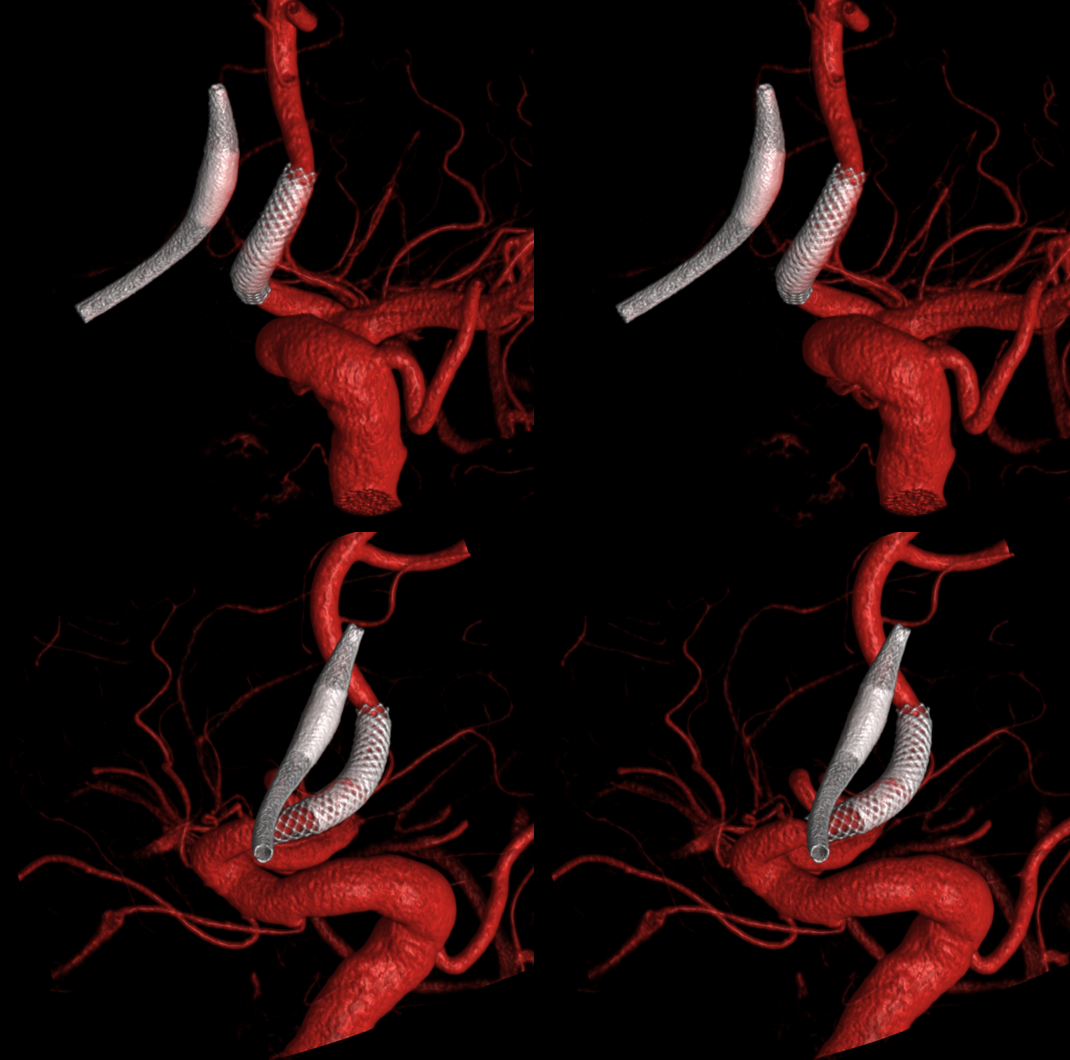

Stereo pairs